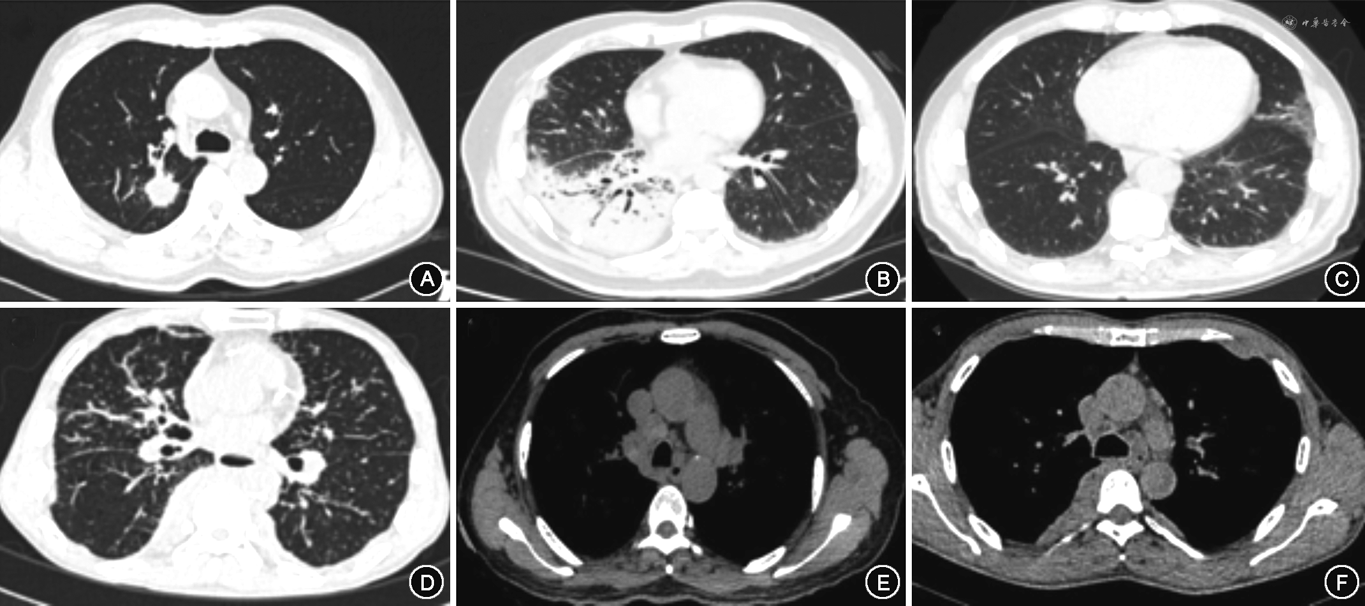

1.影像学表现:60例患者均接受胸部CT检查,其中结节38例,纵隔和(或)肺门淋巴结肿大34例,磨玻璃影31例,小叶间隔增厚29例,支气管血管束增粗28例,实变13例,支气管扩张8例,胸膜增厚18例及椎旁软组织影5例(表3)。其中53例(88.3%)患者存在2种及以上影像学改变。有呼吸系统症状组出现实变影比例均高于无症状组(均P<0.05)。IgG4相关性肺疾病患者胸部CT典型表现见图1。

本研究中,IgG4-RLD患者影像学异常存在高度异质性,涉及气道、肺实质、肺间质、纵隔淋巴结及胸膜多个解剖学部位,且88.3%患者存在2种及以上影像学改变。最常见的影像学改变为结节(63.3%),与国内文献报道一致[14],其次为纵隔和(或)肺门淋巴结肿大(56.7%)、磨玻璃影(51.7%)。另一项针对高加索人种患者的研究发现,最常见的影像学改变为支气管血管束增厚(54%)及纵隔淋巴结肿大(54%),37%患者存在两种以上的影像学改变[15]。由于IgG4-RLD影像学特点缺乏特异性,需与Castleman 病、肺癌、血管炎及结节病等鉴别。